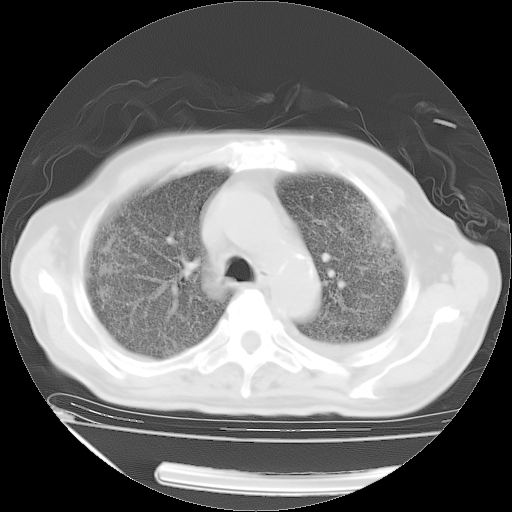

经过24天治疗,岳父的病情基本稳定。生活基本可以自理,可以下床活动。呼吸困难早已消失。体温基本正常。

主要治疗甲强龙80mg×14天,60mg×10天;同时抗结核(异烟肼+利福平+乙胺丁醇)。环磷酰胺0.1 tid 10天。

特别感谢胡教授、高管、桃子版主给出关键的治疗建议。桃版把所有肺部影像和全部临床资料请所在医院呼吸科、感染病科、结核科、临床免疫科专家会诊。临床免疫科专家制定了完整的治疗方案。